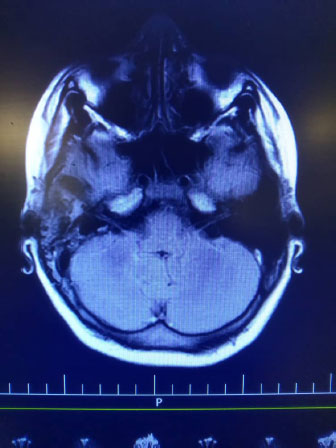

Indeed, high signal intensity in both hemispheres (meningitis), left maxillary and bilateral frontal sinusitis, polyp, and retention cyst in the left maxillary sinus, and right mastoid air cell effusion was reported (Fig. 2).

In spite of mastoid cell opacity, normal audiometry was reported (Fig. 2).

In our opinion a delayed diagnosis of skull fracture induced CSF leak and probably, bacterial meningitis. It is opposed to one study reported in which the skull fracture (either with CSF leak) was resolved spontaneously within 1 to 2 weeks [14, 18-23] Less common presentations include meningitis and seizures [24-27]. The clinical presentation of these cases is similar to other studies [19, 20, 27, 28]. Similar data was reported in a study conducted by Jeevan et al. (2015) [28] In contrast to Carlson et al.’s report [21,27] the presented case with confirmed temporal bone encephalocele had any persistent otorrhea or conductive hearing loss, before admission. In contrast to other studies meningitis and seizures were presented in our case [18, 17]. Unlike other reports, no soft compressible mass was seen in the mastoid cavity [17] Temporal bone encephaloceles are rare in children and usually occur when brain tissue herniates through a Dural defect of the skull. Due to nonspecific signs and symptoms, delays in the diagnosis are usual. Untreated cases could have different side effects such as meningitis, seizures, venous infarction, and intracranial abscess [7-13]. In recent years, in addition to CT scans, Magnetic Resonance Imaging(MRI) was known as the best method for diagnosis of brain tissue herniation in the middle ear cavity [15]. Other imaging modalities such as radio nucleotide cistern gram study may be helpful [15, 16], and could distinguish the encephalocele from other masses (e.g. granulation, cholesteatoma, cholesterol granuloma, etc.) [15]. Usually, multilayered closure of the dura and simultaneous repair of the bone defect is needed in cases with confirmed encephalocele Soft tissue repairs without bone repair result in recurrence in some cases.